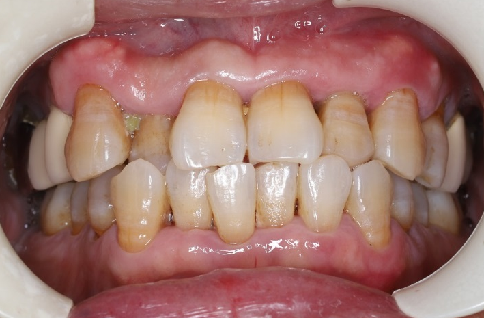

术后5个月完成修复

常规印模制取,应患者要求,术后5个月完成修复。

术前术后对比

由于患者需求因素未进行“即刻临时修复体”的制作和个性化过度义齿试戴,一定程度上影响了术后美学效果的提升。

修复阶段,使用个性化印模制备模型,订制个性化基台螺丝固位,改变了患牙原始的反合情况,尽量纠正为浅覆盖,美观方面有所提升。